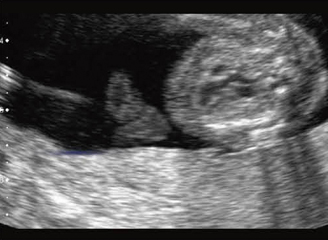

出生後の管理体制により大きく児の予後が左右される疾患に,重症の先天性心疾患がある。胎児心疾患の診断は,ある程度意識を持って診断に当たらねば異常に気が付かない。ここに,胎児の心疾患の診断を特別に考えねばならない理由がある。図7は,NTがあり,単一臍帯動脈,子宮内発育遅延があった。胎児心臓の精査では,大動脈の騎乗が見つかった。出生後の診断はファロー四徴症。

![]() 図7 大動脈騎乗,妊娠27週 染色体検査は正常核型。 ほかに単一臍帯動脈,子宮内発育遅延, 妊娠初期にNTがあった。 |